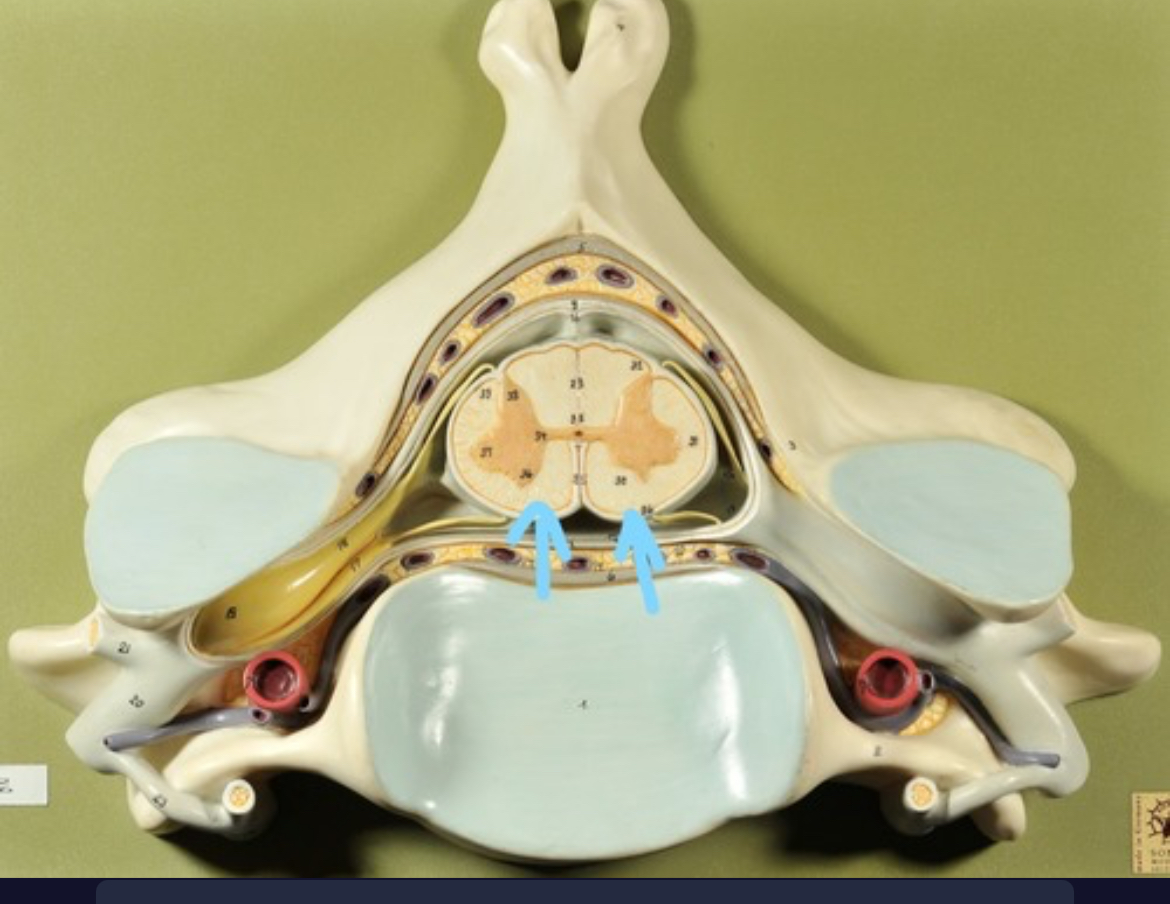

Dura mater (outermost layer)

White matter of spinal cord

Gray matter of spinal cord

Ventral horns (of gray matter)

Lateral horns

Dorsal horns

Anterior columns of white matter

Lateral columns of white matter

Posterior columns of white matter

central canal of spinal cord

Pia matter

Subarachnoid space

Arachnoid matter

Subdural space (brown line)

Dura matter

Epidural space

Dorsal root ganglion

Dorsal root

Ventral root

Spinal nerve